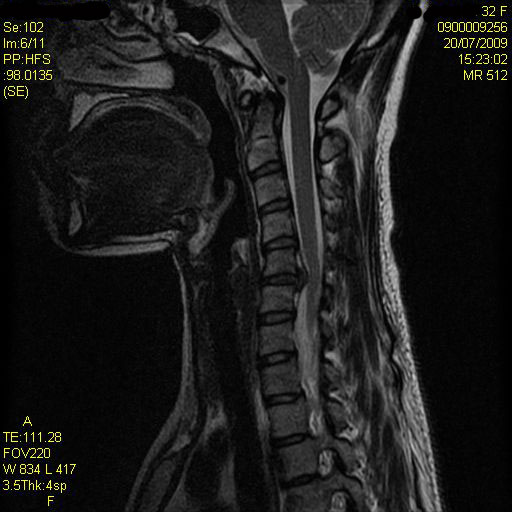

20090527140258 MRIԴϴ. ȸ ϼ. 迵ռ Ȱ ϴٰ ̸ ϴٰ Դϴ. ̷ ص ʾƼ ȸԲ صȰ Ƶ帰 Դϴ. ǰϴ ̳ ȸԲ ð ǥغ Ͽ 2~3 ȣǴ Ȳ Ѻ Ͻö Դϴ. MRIԴϴ. ȸԲ ϼ 159 52 33 ˰Ե ͳ õ ش 4C. 6C.ڸ 6C. κ 6C.ھ Ḳ 1T.ڼյ չٴ 1T.ڼո 1T.ڼհ ü ̳ 1T.Ȳġ 1T. κ 3T.ڵ , 4T. ༺ 4T. 5T.ȯ ҷ, 6T.ڼȭҷ 10T.ٸǷ 3L.ڽѻ Ǵ Ҽ 5L.ڴٸ Ʒκ̳ 5L.ڹ ٸ ȯ ״ ߸ , 5L. , ڸ(߹) Ը Ͽ ũ(߰Ż), ũ(߰Ż)ġ, հ , , հ , ġ, , Ḳ , , Ḳ ġ Ǵ , , ڸ, , ڰ , , Ǵ ġ Ҹ ġ Ƹ ġ Ǹ, Ϸ 2ȸ ̻ ῡ ġ ߷, , нɷ Ʈ 氨 Ǻι̿, Ǻγȭ ָ, ָ, ָ Ǵ ġ ź Ǻ, ȭ ʴ Ǻΰ Ƿ ġ ȭҷ ġ Դ ϰ Ѱ 6 . ǿ ħ 2 ܰġ 1 ȣ ֽϴ. ȸ յ ־.. |